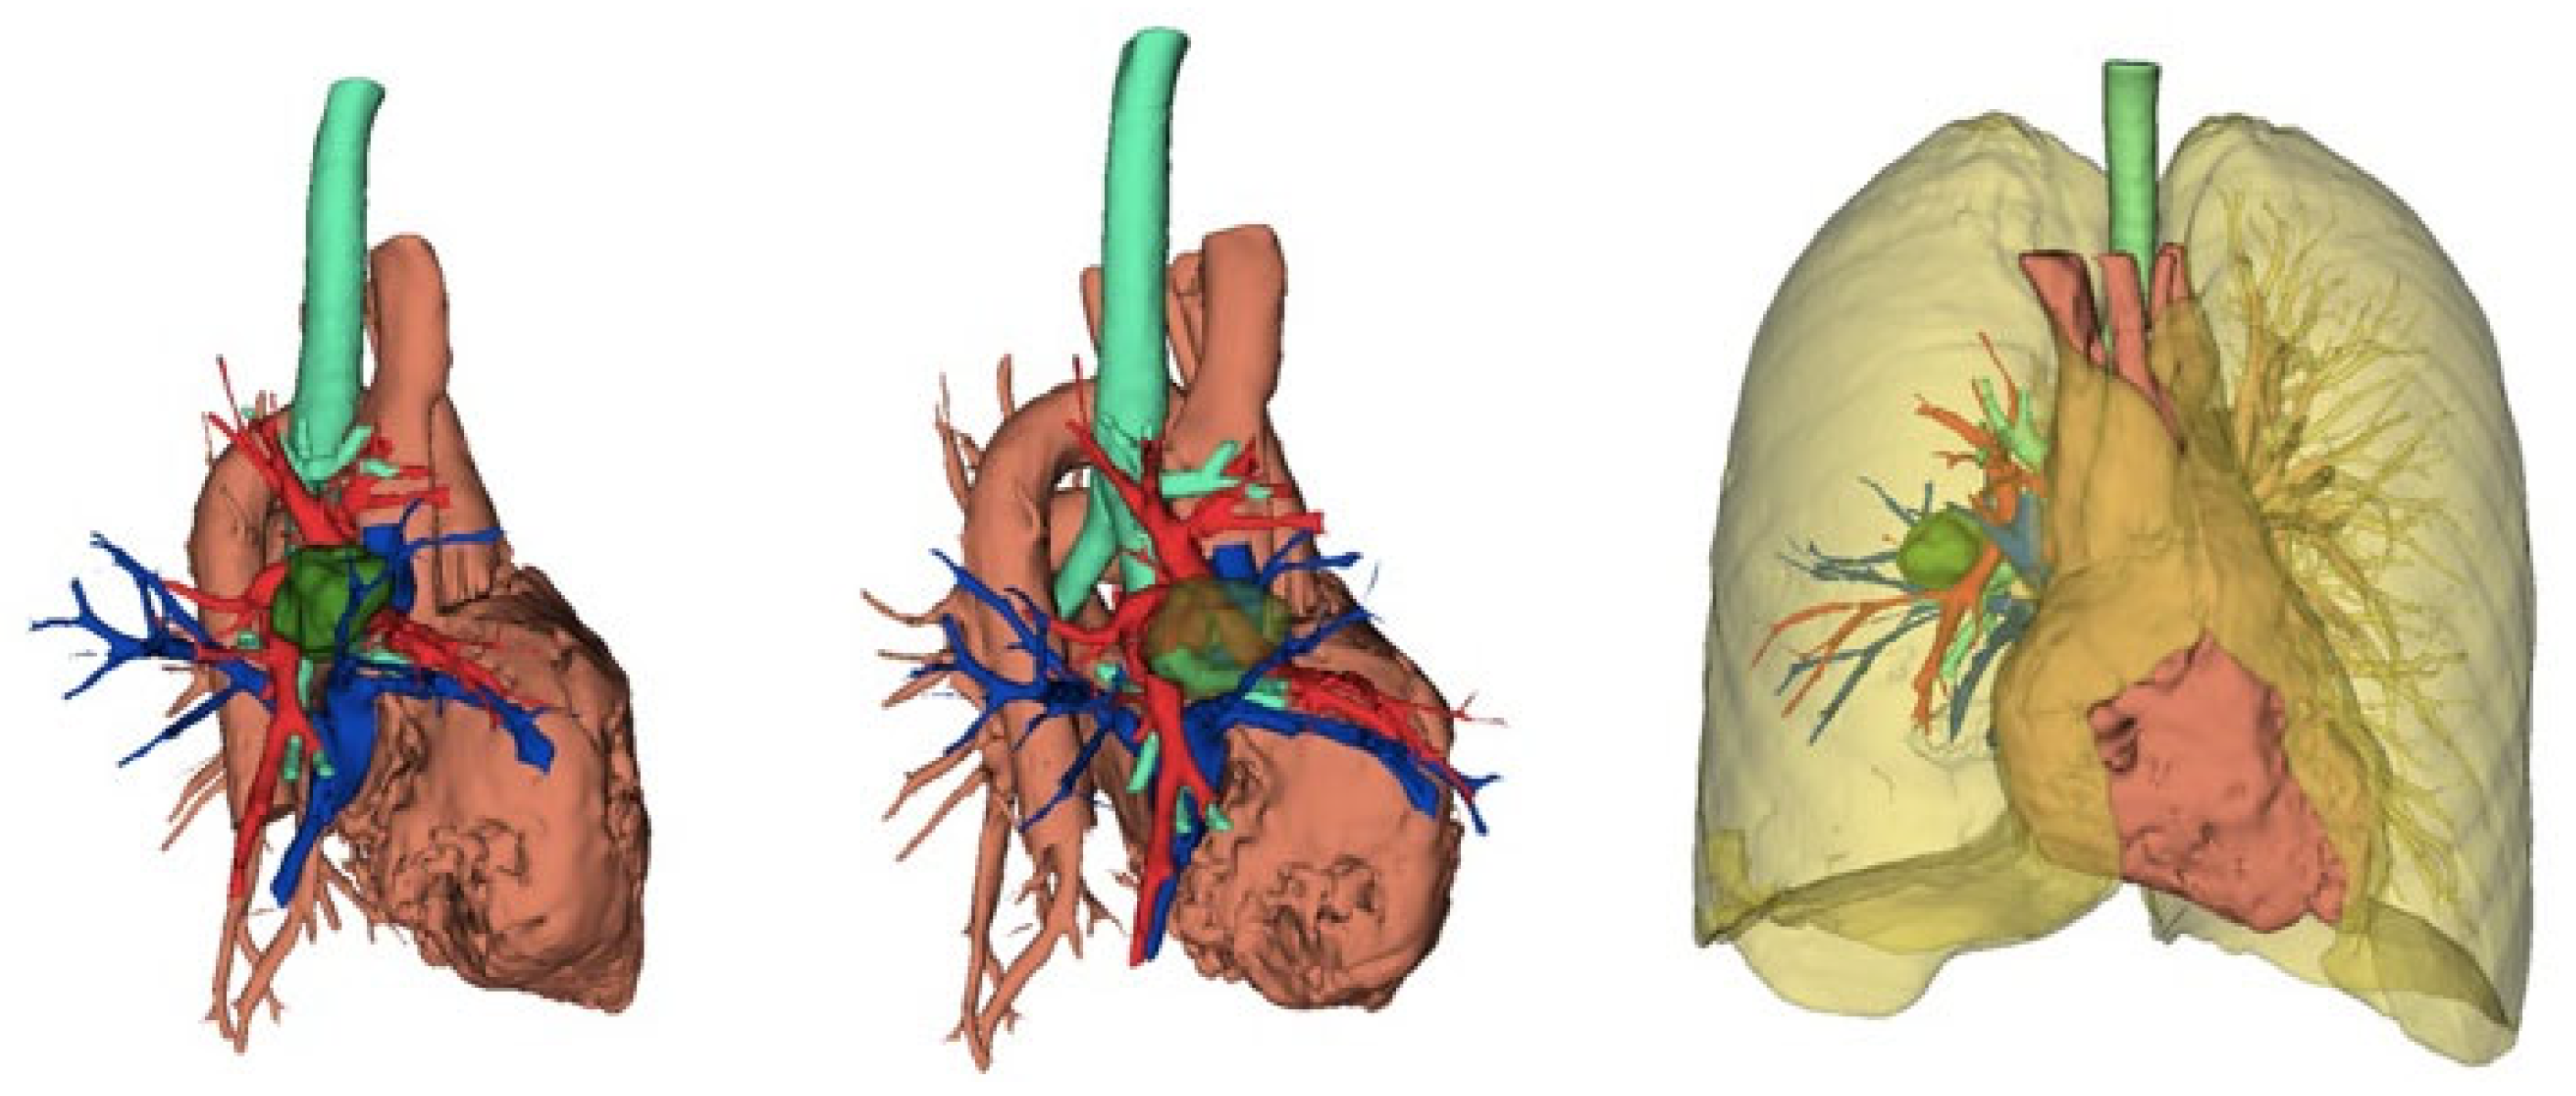

5.1. Preoperative Evaluation and Software in Robotic Surgery

5.2. Role of Advanced Software in Preoperative Planning

5.3. Navigation and Enhanced Visualization

- Ikeda, N.; Yoshimura, A.; Hagiwara, M.; Akata, S.; Saji, H. Three dimensional computed tomography lung modeling is useful in simulation and navigation of lung cancer surgery. Ann. Thorac. Cardiovasc. Surg. 2013, 19, 1–5. [Google Scholar] [CrossRef] [PubMed]

- Chen-Yoshikawa, T.F.; Date, H. Update on three-dimensional image reconstruction for preoperative simulation in thoracic surgery. J. Thorac. Dis. 2016, 8 (Suppl. S3), S295–S301. [Google Scholar] [CrossRef]